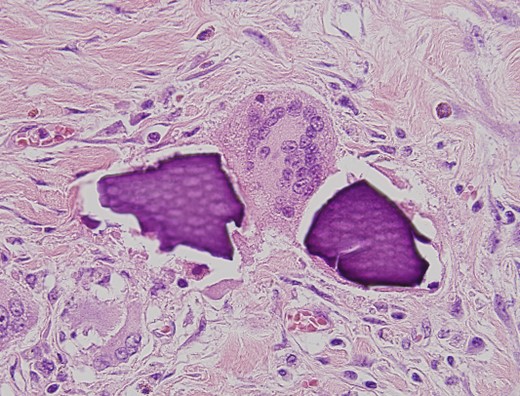

Microscopic pathological examination: abundant calcium polystyrene sulfonate crystals along the intestinal wall surrounded by intense inflammatory infiltrate.

Multinucleate giant cell trying to phagocytize calcium polystyrene crystals.